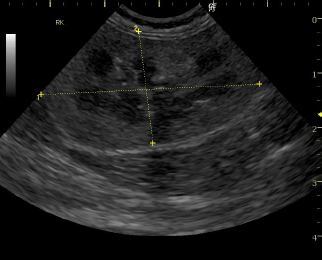

上側が手術前、下側が手術後のエコー画像です。

手術前は尿が腎臓内に溜まってしまい水腎症の状態ですが(黄色矢印の黒い部分が流れないで溜まっている尿です)、術後正常な腎臓の構造に戻っている事が確認できました。 手術後は尿も流れるようになり、体調も回復し元気に退院できました。 |